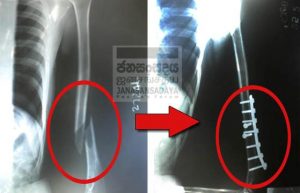

Mohan was admitted to the Peradeniya Teaching Hospital and underwent an X-ray examination and the doctors informed the relatives that there was an oblique fracture (please see X-ray above) due to the tortured he suffered. Mohan had to undergo surgery to treat the fracture and a plate and pins were inserted. Mohan was instructed to attend the orthopedic clinic of the Peradeniya Teaching Hospital for further treatment.

Mohan was admitted to the Peradeniya Teaching Hospital and underwent an X-ray examination and the doctors informed the relatives that there was an oblique fractured (please see X-ray above) due to the tortured he suffered. Mohan had to undergo surgery to treat the fracture and a plate and pins were inserted. Mohan was instructed to attend the orthopedic clinic of the Peradeniya Teaching Hospital for further treatment.